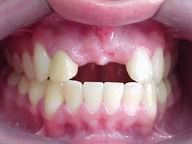

| Antes: Prótese removível provisória, conforme se apresentou à primeira consulta |

Depois: Próteses cerâmicas ao final do tratamento |